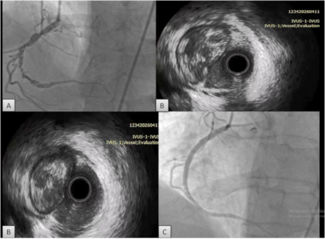

Case Report 2. A 45-year-old woman with a history of right-sided breast cancer diagnosed 1 year prior to her admission presented to an outside hospital with a 6-week history of slowly progressing neck, facial, breast swelling, and shortness of breath. A CT scan of the chest showed near complete occlusion of the superior vena cava. Patient was transferred to our center for further management. She had received multiple upper extremity ports and catheters over the last year and had a left subclavian line still in place upon presentation.  A venogram was obtained using her left subclavian port. The SVC, RIJ, and right brachiocephalic vein were occluded (Figure 4). The right internal mammary vein was large and provided many venous collaterals. We then accessed the right femoral vein, introduced a 10 cm 8 Fr Pinnacle sheath (Terumo) and crossed the obstruction using a 0.035 Glidewire (Terumo) and a 5 Fr angled-tip Berenstein catheter (AngioDynamics). After confirming we were in the true lumen of the RIJ, we exchanged for a Rosen wire

A venogram was obtained using her left subclavian port. The SVC, RIJ, and right brachiocephalic vein were occluded (Figure 4). The right internal mammary vein was large and provided many venous collaterals. We then accessed the right femoral vein, introduced a 10 cm 8 Fr Pinnacle sheath (Terumo) and crossed the obstruction using a 0.035 Glidewire (Terumo) and a 5 Fr angled-tip Berenstein catheter (AngioDynamics). After confirming we were in the true lumen of the RIJ, we exchanged for a Rosen wire  (Infiniti Medical) and introduced an 8 Fr Trellis device with a 15 cm treatment zone. After isolating the segment between the RIJ and the SVC/right atrial junction (Figure 5), we infused 11 mg of t-PA over 12 minutes. Following restoration of flow, a severe stricture was seen in the SVC and the brachiocephalic vein. We then dilated the brachiocephalic vein using an 8 mm x 60 mm Agiltrac balloon (Abbott) at 6 and 12 atm, and dilated the SVC using a 12 mm x 40 mm Foxcross balloon (Abbott) at 8 atm in graded increases of 4 atm. We checked for a pressure gradient between the RIJ and the right atrium using a 6 Fr multipurpose catheter (Boston Scientific), a 0.018 wire, and a Tuohy system (Boston Scientific). The maximal pressure difference was less than 5 mmHg. A venogram was performed and showed good flow restoration across the brachiocephalic and SVC (Figure 6). Patient felt a decrease in her neck swelling and shortness of breath while on the table within a few minutes following the end of the procedure. She was still asymptomatic and feeling great at 3 months follow-up and was later seen by her primary oncologist for continued work-up for cancer.

(Infiniti Medical) and introduced an 8 Fr Trellis device with a 15 cm treatment zone. After isolating the segment between the RIJ and the SVC/right atrial junction (Figure 5), we infused 11 mg of t-PA over 12 minutes. Following restoration of flow, a severe stricture was seen in the SVC and the brachiocephalic vein. We then dilated the brachiocephalic vein using an 8 mm x 60 mm Agiltrac balloon (Abbott) at 6 and 12 atm, and dilated the SVC using a 12 mm x 40 mm Foxcross balloon (Abbott) at 8 atm in graded increases of 4 atm. We checked for a pressure gradient between the RIJ and the right atrium using a 6 Fr multipurpose catheter (Boston Scientific), a 0.018 wire, and a Tuohy system (Boston Scientific). The maximal pressure difference was less than 5 mmHg. A venogram was performed and showed good flow restoration across the brachiocephalic and SVC (Figure 6). Patient felt a decrease in her neck swelling and shortness of breath while on the table within a few minutes following the end of the procedure. She was still asymptomatic and feeling great at 3 months follow-up and was later seen by her primary oncologist for continued work-up for cancer.